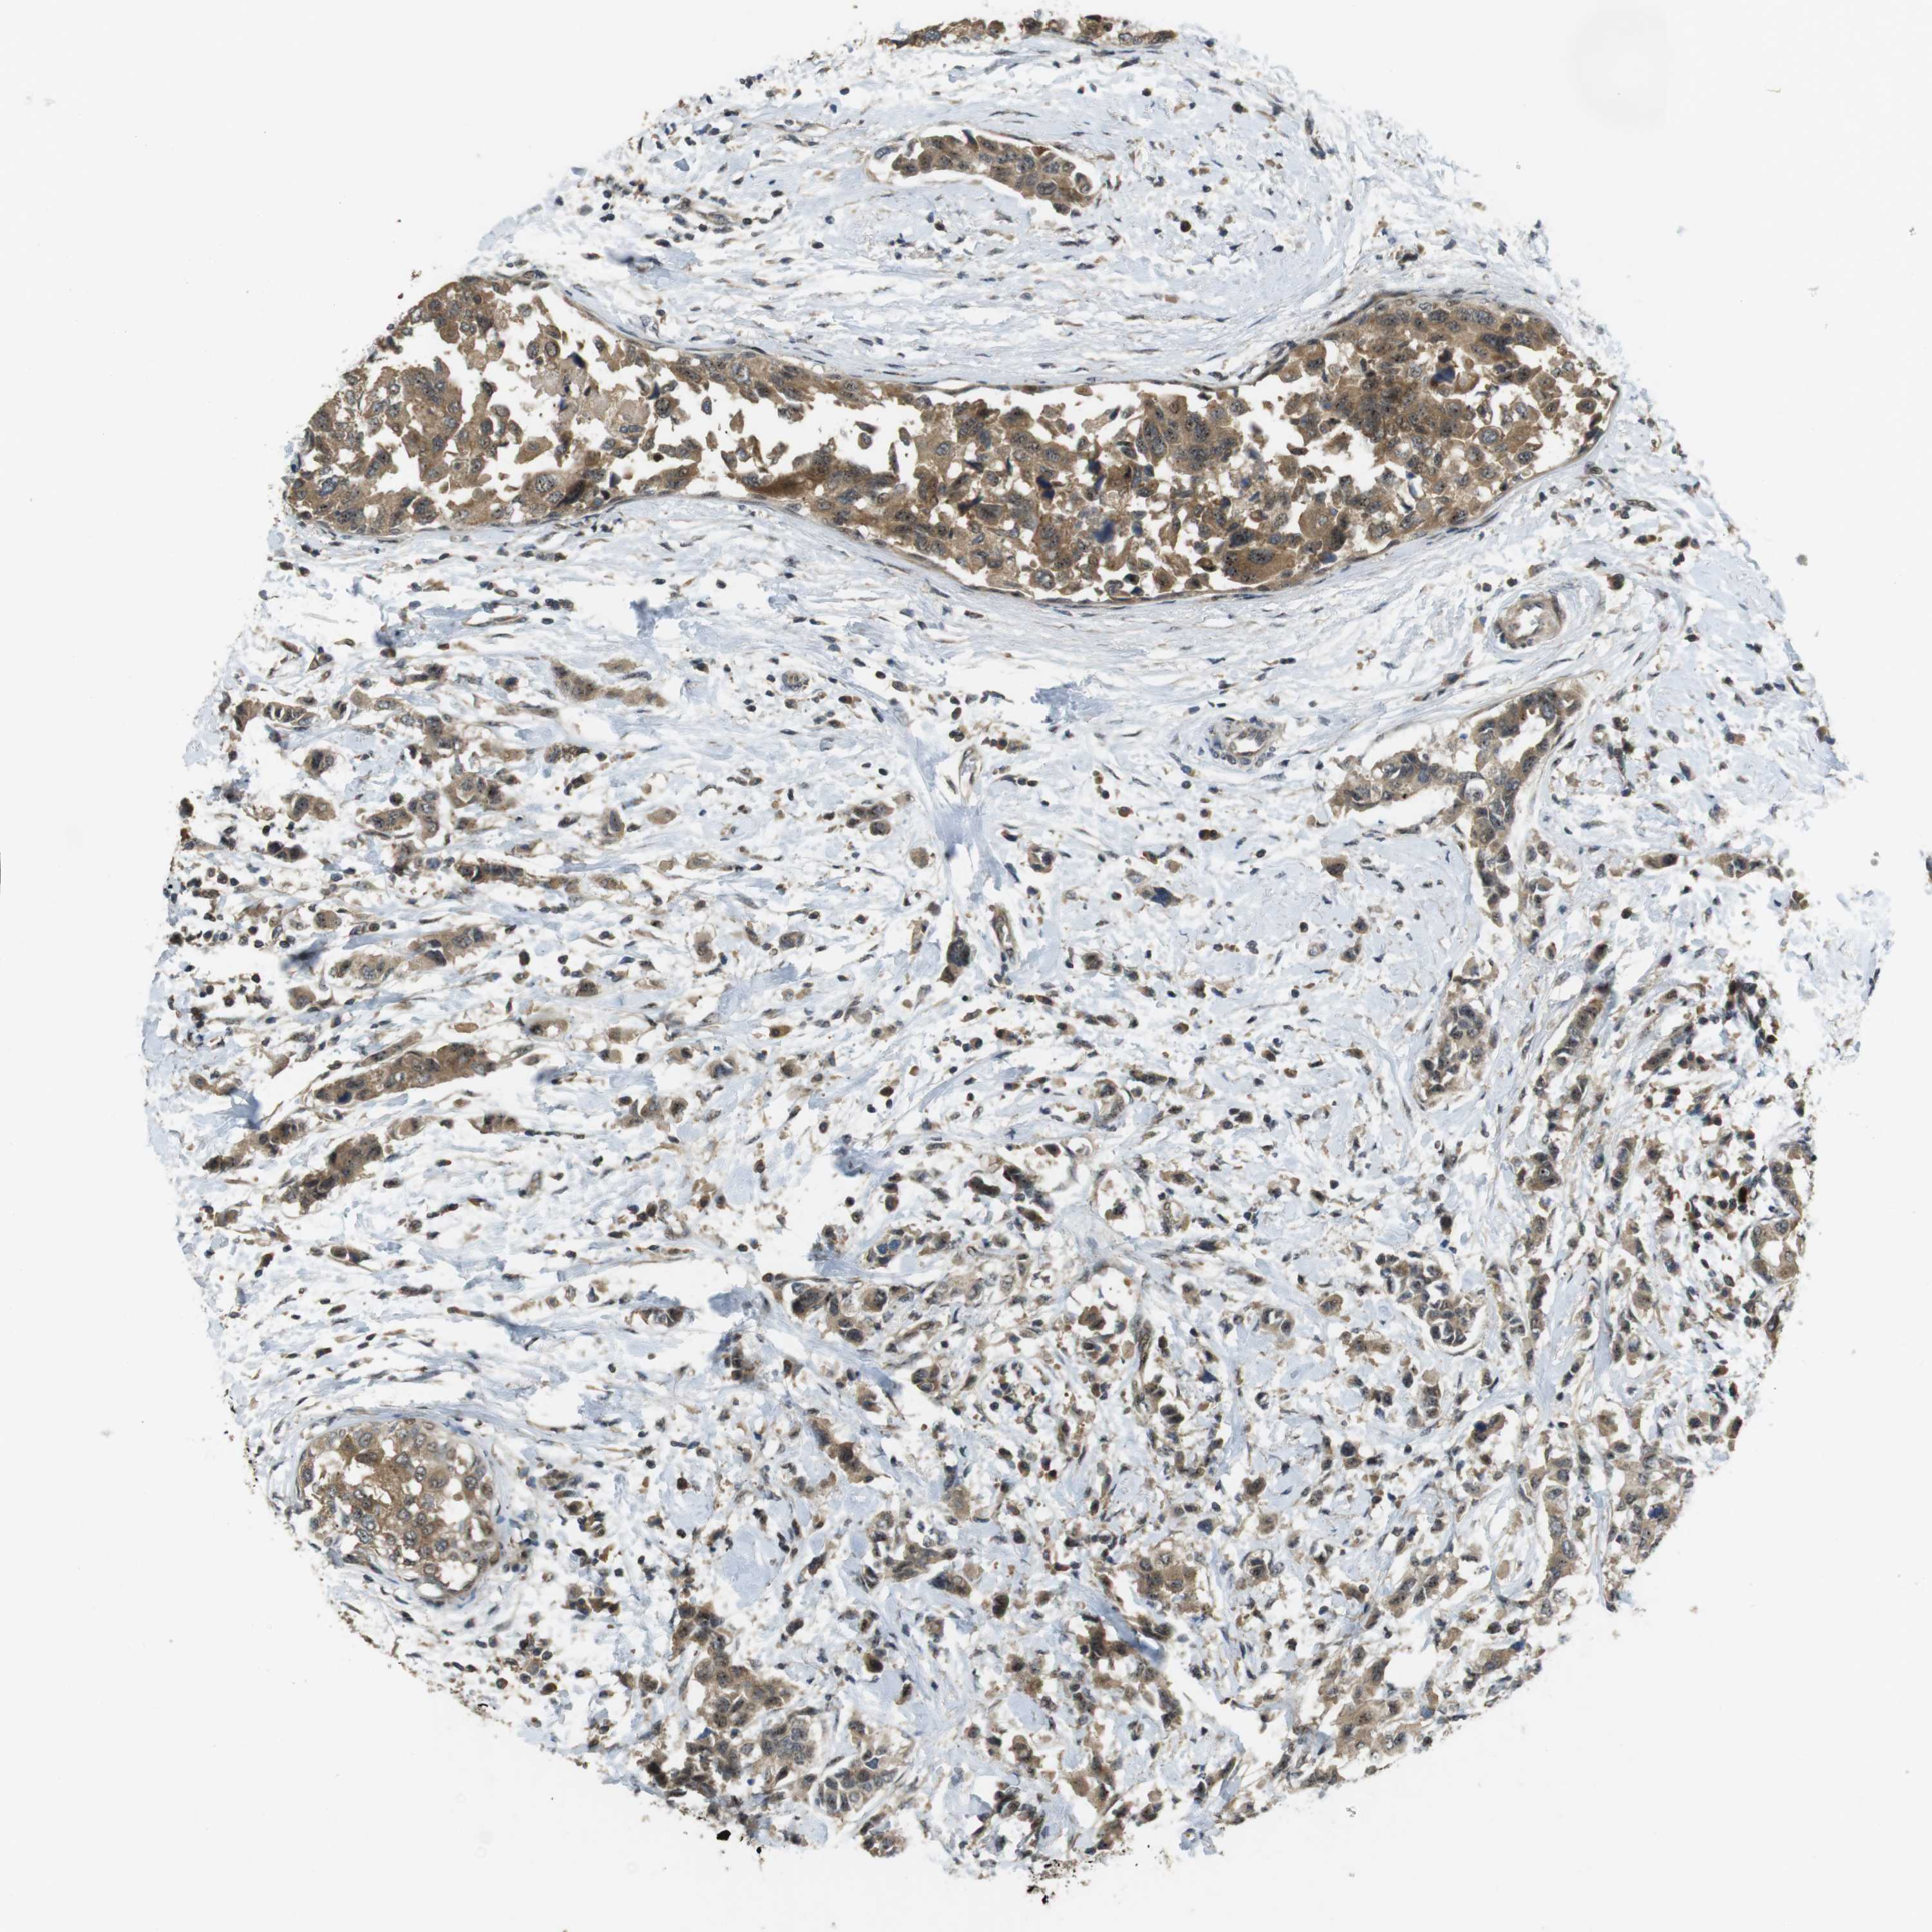

BRCA TCGA BRCA VALIDATION PROTEIN EXPRESSION

Breast cancer

Human cancer